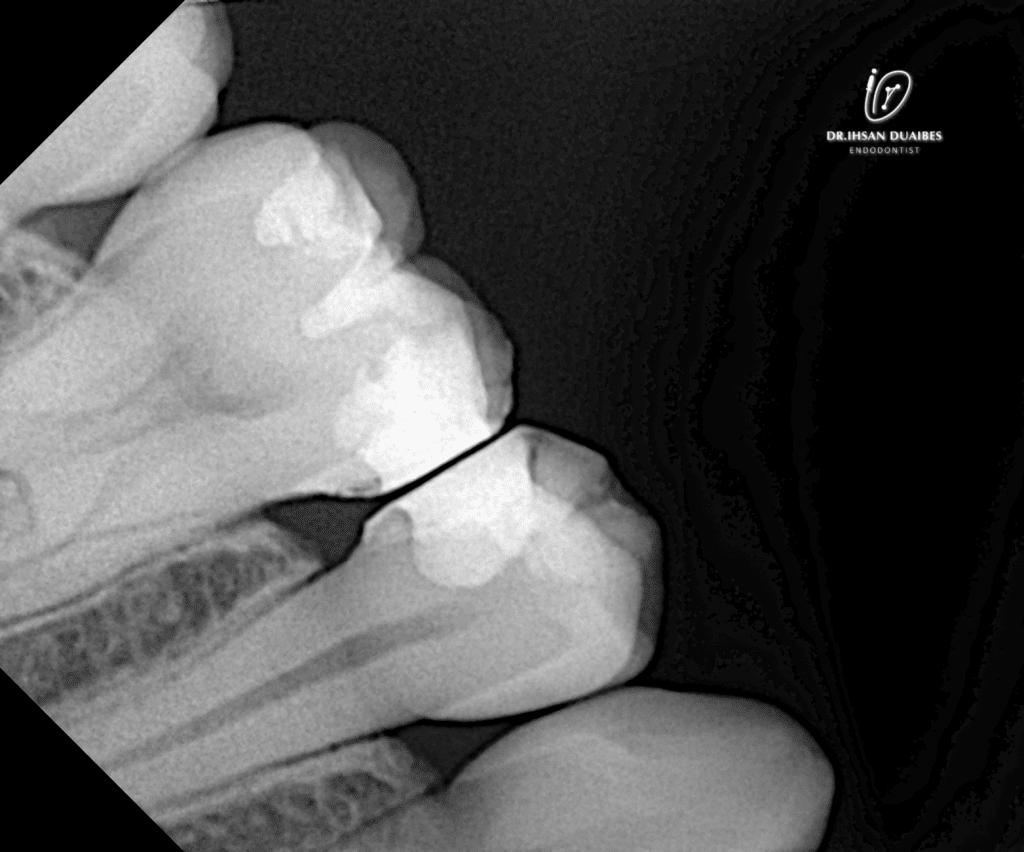

X-ray